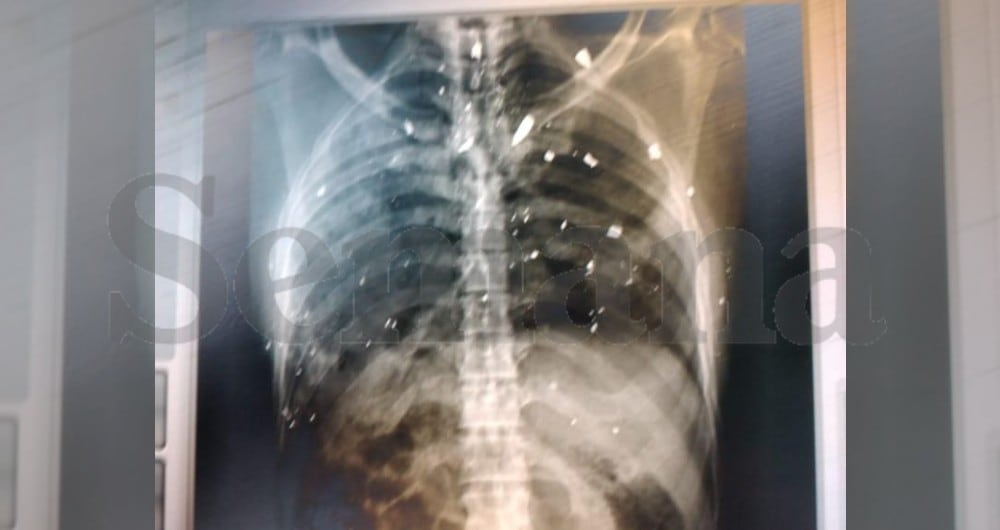

SEMANA también obtuvo todas las radiografías que le tomaron al cadáver del mandatario. El crimen, sin duda, fue cometido con mucho odio, a juzgar por las imágenes. En una primera placa se ve el cráneo con dos impactos de bala que lo atraviesan, uno de ellos en la parte superior y otro en la base. El informe forense confirmó que los disparos impactaron el hueso frontal y el hueso parietal. Los médicos también concluyeron que el presidente, sin duda, recibió un golpe final, cuando ya estaba acostado de espaldas.

La imagen de la radiografía del pecho también muestra varios impactos en diferentes lugares. Todo este material forense está en poder de las autoridades haitianas. Los resultados del estudio del cuerpo evidencian lo que se denunció desde el principio: el uso de una violencia extrema contra el primer mandatario, quien no pudo hacer nada para defenderse. Moïse fue golpeado salvajemente, aun cuando ya estaba moribundo.

El informe forense había relatado de una manera muy cruda la escena del crimen que vio esa madrugada del 7 de julio: “Lo encontramos acostado boca arriba: pantalón azul, camisa blanca manchada de sangre, boca abierta, ojo izquierdo perforado. Vimos un agujero de bala en la frente, uno en cada pezón, tres en la cadera, uno en el abdomen”.